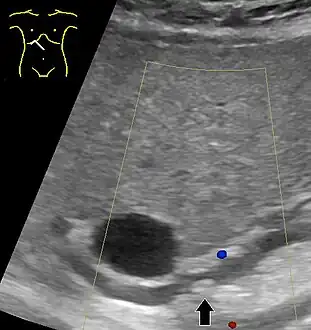

- Abdominal ultrasonography of a common bile duct stone